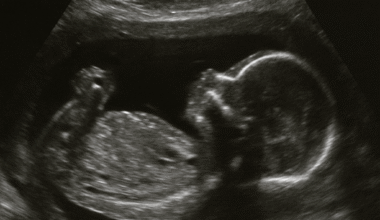

But the most magical part of this trimester came at 21 weeks, when I felt my baby’s first movements. At first, it was just a little flutter. Almost like butterfly wings brushing against me from the inside. I wasn’t even sure if it was real at first, but as it happened more and more, I knew it was my baby.

“In that moment, I felt so happy, so thankful, and so deeply connected to the little life growing inside me.”

It’s hard to put into words how powerful that feeling was. All the nausea, all the fatigue, all the worries—they seemed to fade in the background when I realized there was a tiny human moving around, reminding me every day that I wasn’t alone.